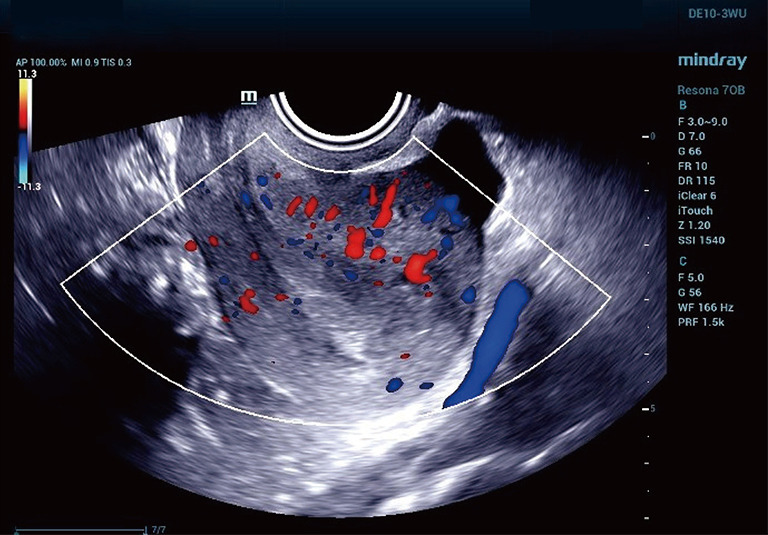

Case description: A 24-year-old female presented with amenorrhea for over 40 days, and tested positive for urine hCG using the colloidal gold method (124 IU/L). However, her serum β-hCG measured by electrochemiluminescence was <0.200 IU/L, and her progesterone was 29.3 nmol/L. A further analysis across platforms revealed that the Roche, Beckman, and Mindray chemiluminescence methods were unaffected by rhIFN-α2b, while the colloidal gold urine hCG, quantitative immunochromatography, and Abbott chemiluminescence assays were affected by rhIFN-α2b. This interference likely stems from the immunomodulatory effects of rhIFN-α2b, which can cause non-specific binding to assay antibodies.